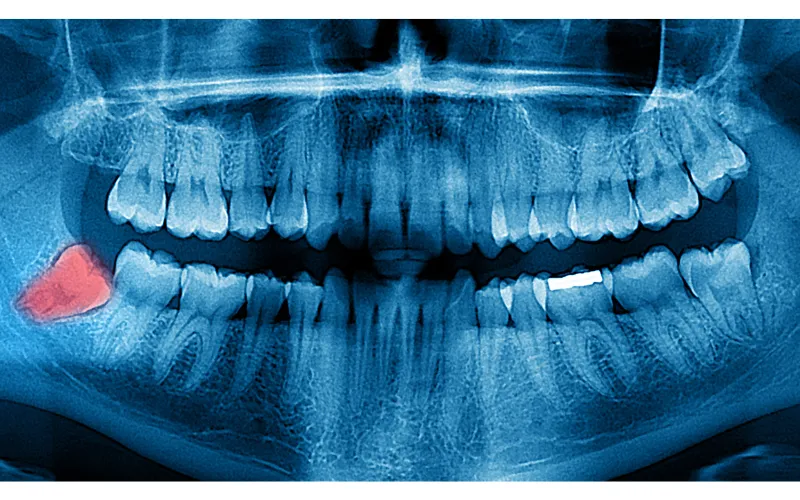

Priprava: Pred posegom lahko opravimo rentgenski pregled, da natančno ocenimo položaj zoba, ki ga bomo ekstrahirali. Na posvetu izberemo tudi ustrezno anestezijo, da je postopek čim manj neprijeten.

Ekstrakcija: V dlesni naredimo rez, da razkrijemo zob in kost. Če je potrebno, odstranimo del kosti, ki zakriva zob. Zob odstranimo cel ali v delih, odvisno od njegove pozicije in stanja.